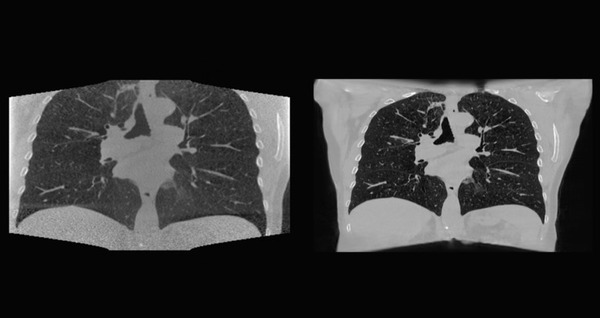

オランダがん研究所 NVIDIA AI Enterpriseで腫瘍の位置を特定できるディープラーニングモデルを構築 2枚目の写真・画像

オランダがん研究所 NVIDIA AI Enterpriseで腫瘍の位置を特定できるディープラーニングモデルを構築